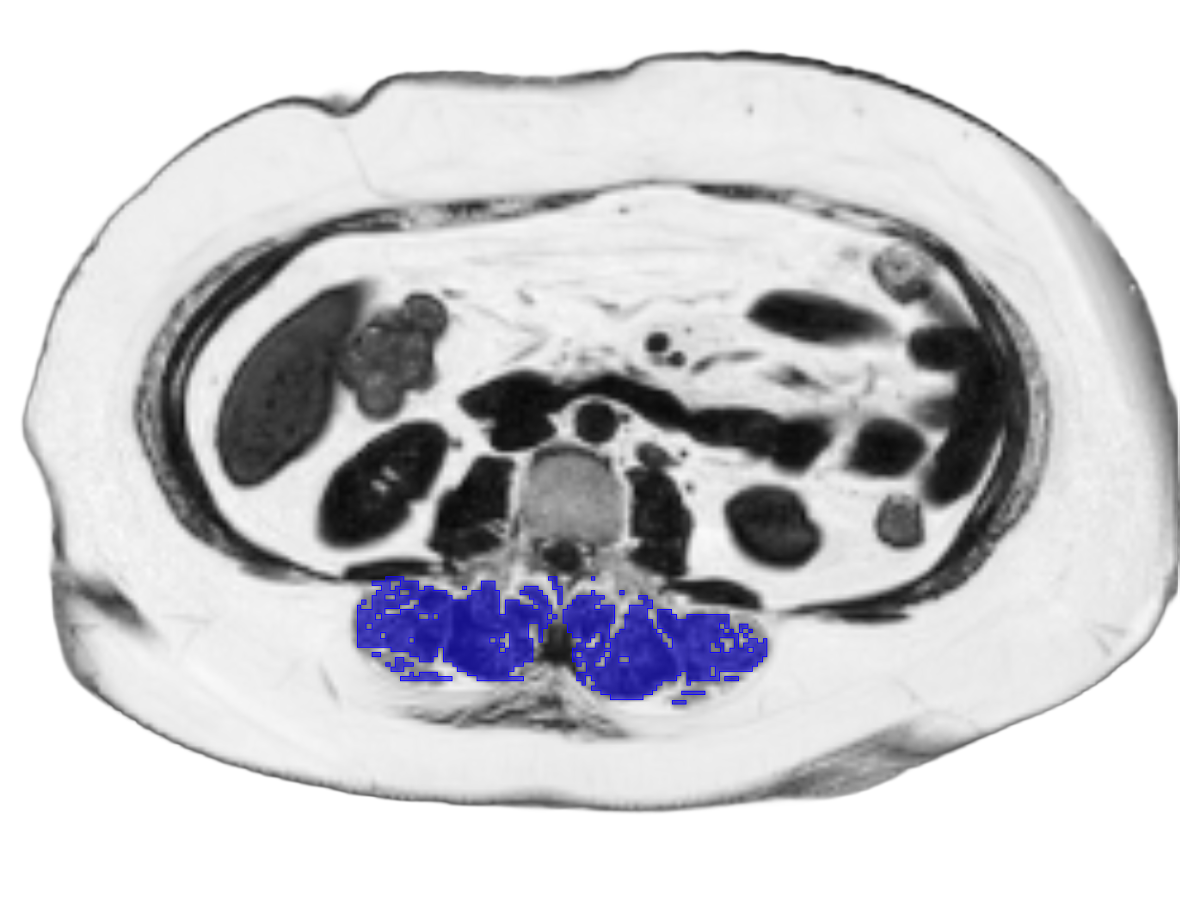

We provide neck-to-knee MRI body composition metrics including visceral (VAT) and subcutaneous adipose tissue (SAT), lean tissue volume, skeletal muscle volume and index, muscle fat infiltration (MFI), and suspected brown adipose tissue (sBAT).

Ectopic fat – impairs organ health and is one of major factors in cardiometabolic disease development

MRI body composition

Skeletal muscle

Visceral adipose tissue (VAT)

Subcutaneous adipose tissue (SAT)

Suspected brown adipose tissue (sBAT)

Muscle fat infiltration (MFI)

Multi-organ ectopic fat

Pericardial fat

Epicardial fat

Liver fat PDFF

Pancreatic fat PDFF

Peri-renal fat

Renal sinus fat